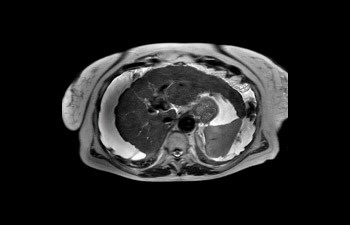

Mayor fiabilidad diagnóstica en neurooncología